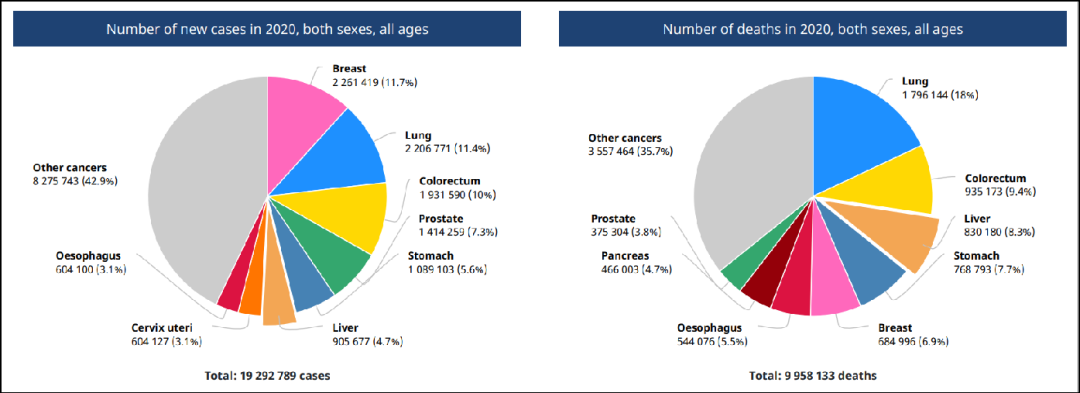

我国是肝癌大国,每年都有不少人因为得了肝癌而痛苦地生活着。而肝癌的治疗,绝对是一场与时间赛跑的生命之战,只有早发现、早确诊、早治疗,才能为战胜癌症病魔获取多一分胜算。